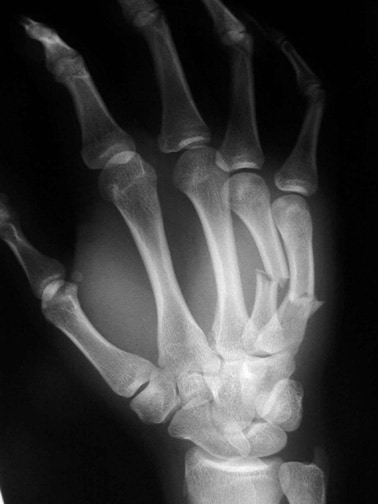

Here's that scan of the x-ray you asked for:

LOL! That looks like an injury from slugging something solid. Like a wall. :eek:

Danny, you need to learn how to punch, hit with knuckles for index and middle finger to avoid the boxer's fracture.

That guy (it's alway a guy) could have used some percutaneous pinning. There's a fair amount of soft tissue swelling, too.